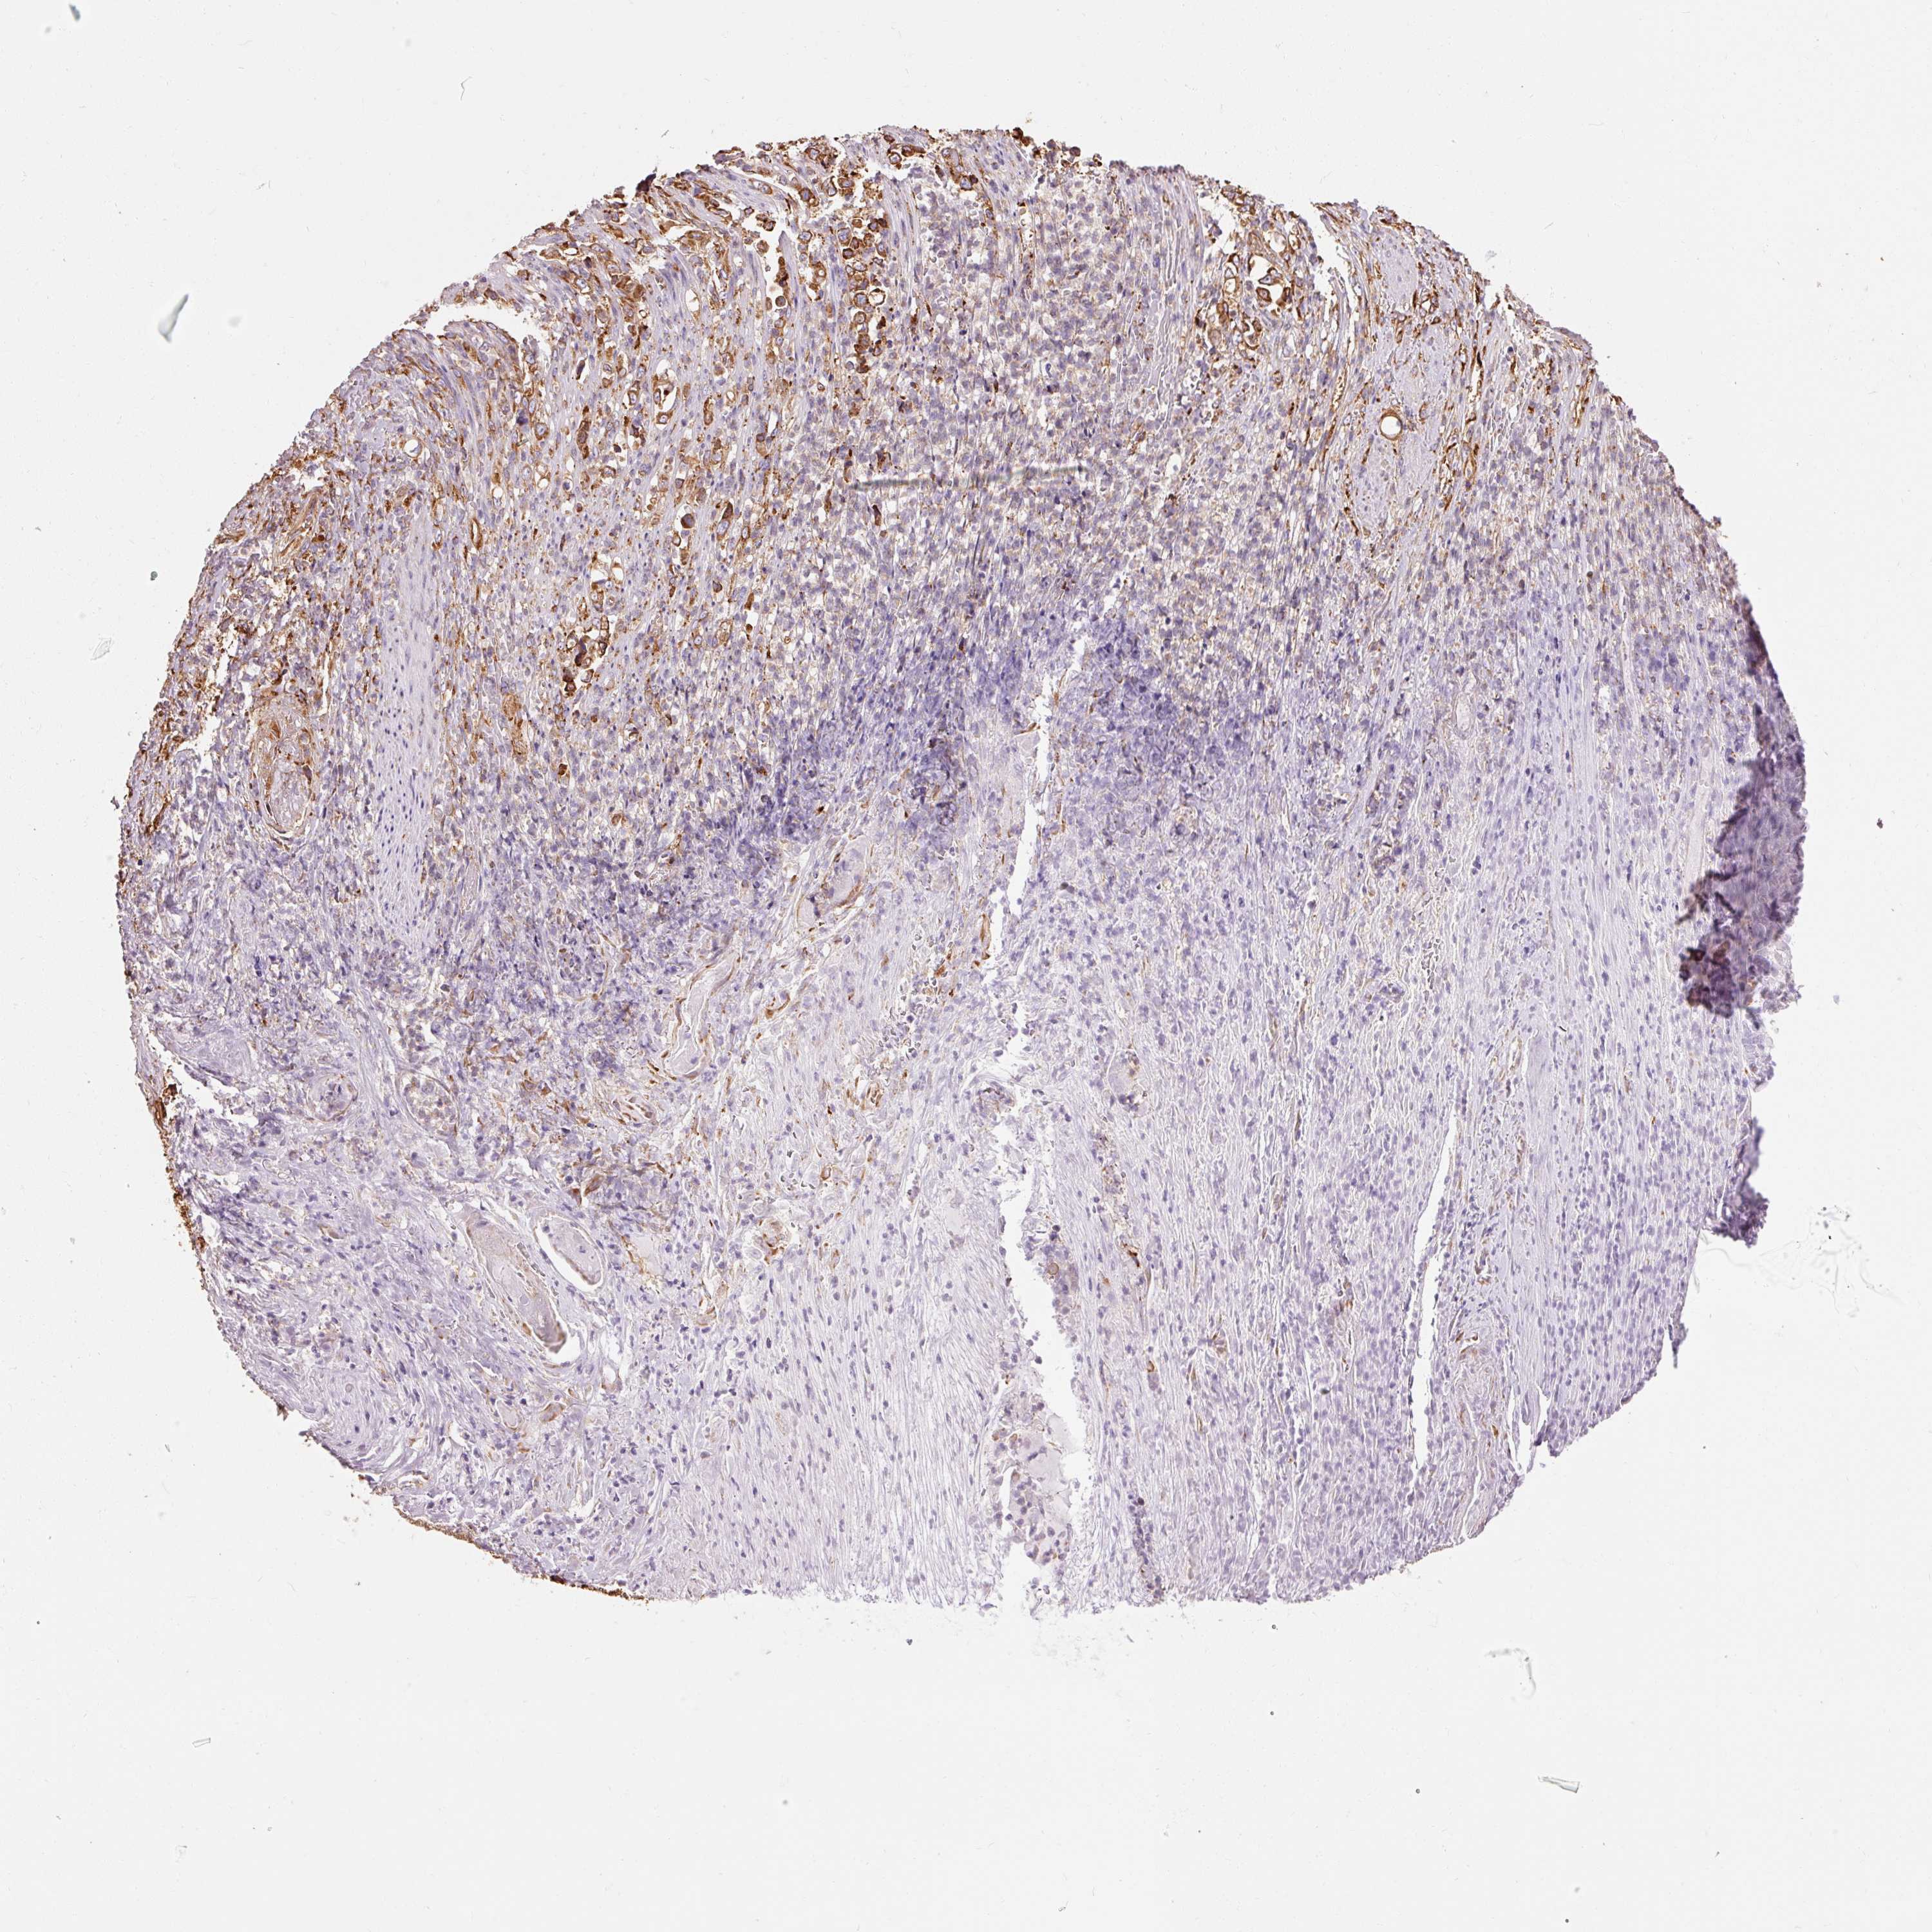

STOMACH CANCER - Protein expressioni

A mouse-over function shows sample information and annotation data. Click on an image to view it in a full screen mode. Samples can be filtered based on level of antibody staining by selecting one or several of the following categories: high, medium, low and not detected. The assay and annotation is described here.

Note that samples used for immunohistochemistry by the Human Protein Atlas do not correspond to samples in the TCGA dataset.

Antibody stainingi

Antibody staining in the annotated cell types in the current human tissue is reported as not detected, low, medium, or high, based on conventional immunohistochemistry profiling in selected tissues. This score is based on the combination of the staining intensity and fraction of stained cells.

Each image is clickable and will lead to virtual microscopy that enables deeper exploration of all samples and also displays staining intensity scores, fraction scores and subcellular localization as well as patient and tissue information for each sample.

Antibody HPA044617

Antibody HPA052450

Staining

High

Medium

Low

Not detected

Intensity

Strong

Moderate

Weak

Negative

Quantity

>75%

75%-25%

<25%

None

Location

Nuclear

Cytoplasmic/membranous

Cytoplasmic/membranous,nuclear

Adenocarcinoma, NOS